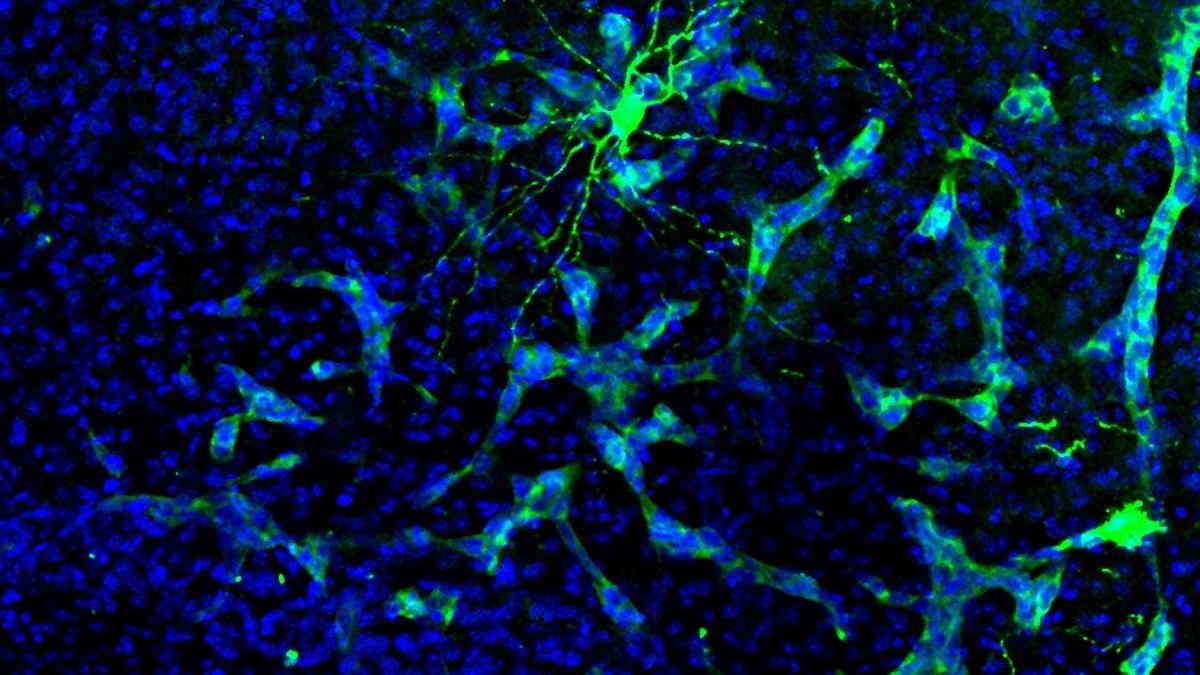

Científicos españoles han comenzado a descifrar cómo se producen las alteraciones cognitivas que sufren los pacientes con metástasis cerebral, lo que abre prometedoras líneas de investigación tanto para mejorar la calidad de vida de estas personas como para la detección precoz de la metástasis.

El estudio, que protagoniza este miércoles la portada de la revista científica 'Cancer Cell', es fruto de una investigación multidisciplinar liderada por investigadores del Consejo Superior de Investigaciones Científicas (CSIC) y del Centro Nacional de Investigaciones Oncológicas (CNIO), que han concluido que los tumores cerebrales "hackean" la comunicación entre neuronas.

A través de experimentos del comportamiento de tres tipos de metástasis (de cáncer de pulmón, mama y melanoma) en ratones y de análisis computacionales e inteligencia artificial, los investigadores han visto que cuando el cáncer produce metástasis en el cerebro altera la química cerebral, e interfiere en la comunicación neuronal (las neuronas se comunican mediante impulsos eléctricos).

Al medir la actividad eléctrica del cerebro de ratones con y sin metástasis, observaron que los registros electrofisiológicos eran totalmente distintos.

"Solo mirando la actividad neuronal, podíamos predecir si había metástasis en el cerebro o no, y, si la había, qué tipo de metástasis era", ha señalado Valiente.

En definitiva, los científicos han constatado que la metástasis deja una huella muy clara en la actividad cerebral, lo que "abre enormes posibilidades" hacia hallazgos importantes, como por ejemplo la detección de la metástasis en un estado muy inicial, ha agregado Valiente.